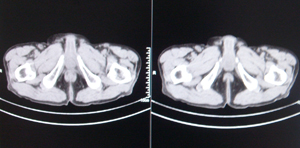

前列腺癌术后10余年,复查有无复发,请指教,图像做得不好,还望包涵

膀胱内可见占位,建议膀胱镜观察

像膀胱内占位

前列腺增大,向上突入膀胱内,结合病史考虑前列腺癌复发可能。

图像太小,左侧膀胱壁似见不规则突起,前列腺突入膀胱,建议膀胱镜检查及前列腺增强检查。